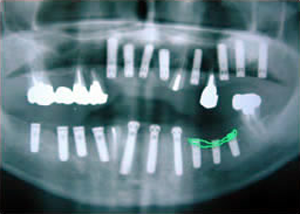

症例1 51歳男性

2007 9/14 更新

治療前

平成16年7月7日

1.・骨つくり

・インプラント15本埋入

ソケットリフト

サイナスリフト

リッジオギュメンテーション

2.上7本インプラントに土台をつけたところ

-2-口腔内写真

-2-仮歯12本入れたところ

-2-仮歯12本入れたところ(正面)

3.仮歯上12本

下15本入れたところ(正面)

4.下14本最終の冠をかぶせたところ-上から(鏡)

-正面-下14本の最終の冠をかぶせたところ

5.終了時レントゲン

治療完了

平成19年5月1日

(治療期間:2年10ヶ月)